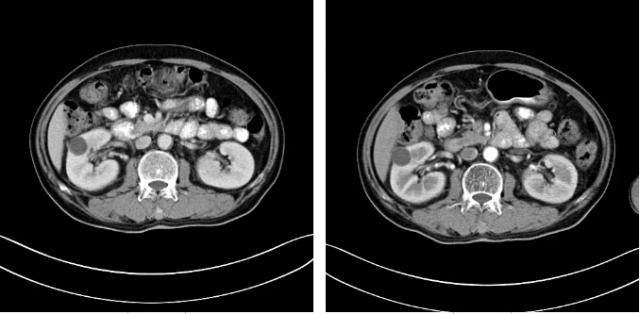

隨著時間的推移,安圖叔叔身體開始發(fā)生明顯變化,腰疼的癥狀得到緩解,血尿的次數(shù)明顯減少,睡眠質量有明顯的改善。以前上廁所都是一件很痛苦事情,如今逐漸正常。安圖叔叔的病情得到改善,在一次次的復查中得到主治醫(yī)生王峰的佐證。過去的兩年里,安圖叔叔一直遵循醫(yī)生的囑咐,按時服藥定時回院復查,到目前為止是安圖叔叔第9次來院復查。安圖叔叔的兒子說道:“我每次帶父親來檢查都有新發(fā)現(xiàn),腫瘤在一天天的變小,我們很相信醫(yī)生的話,他們會給我們最好的治療方案,如今已過去兩年,父親身體和精神慢慢轉好,這是我們所希望的!

自2017年做冷凍消融術后,安圖叔叔兩年多時間腫瘤不僅沒有增長并多次檢查沒有復發(fā)跡象。安圖叔叔認為,冷凍給他帶來新的希望,又一次看到復大創(chuàng)造新的奇跡。